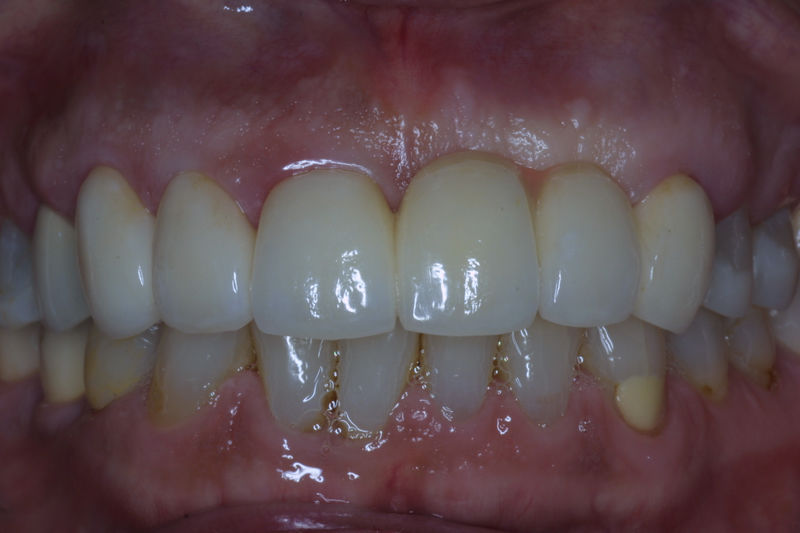

Amplia gama de tratamientos para mejorar la apariencia de la sonrisa, corrigiendo el color, la forma, el tamaño, la alineación y la posición de los dientes. Los procedimientos más comunes y solicitados incluyen el blanqueamiento dental, las carillas y coronas, así como las resinas.